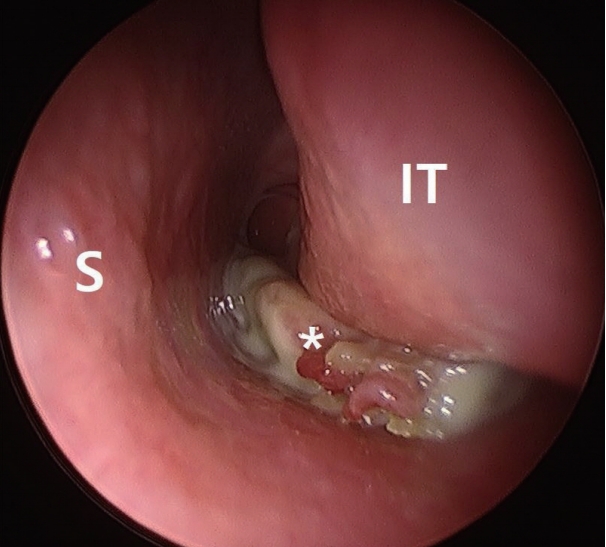

증 례65세 여자 환자가 2주 전부터 시작된 좌측 코막힘과 화농성 비루를 주소로 내원하였다. 고혈압으로 약물 치료 중이었으며 그 외 내과적 기저 질환은 없었다. 비내시경 검사에서 화농성 분비물을 동반한 경계가 불규칙적인 종물이 좌측 하비도의 후방을 채우며 후비공까지 진행되어 있었고, 종물 주변으로 하비갑개와 하비도 점막의 비후가 관찰되었다(Fig. 1).

Fig. 1.Preoperative endoscopic findings. A bizarre single polypoid mass (*) is located between the left inferior turbinate and the basal floor of the nasal cavity. S: septum, IT: inferior turbinate. Fig. 2. Preoperative CT findings. Axial (A) and coronal (B) view. CT shows soft tissue density at the basal floor of the nasal cavity. Bone erosion is not observed and paranasal sinus is clear. Fig. 3.Preoperative MRI findings. Axial (A) and coronal (B) view. An ovoid homogenous enhancing mass (arrowhead) appears to originate from the posterior inferior side of the left inferior turbinate (arrow) and extends to the choana. Fig. 4. Operative findings. A pedicle (arrow) of single polypoid mass (*) is attached to the posterior side of the inferior turbinate. REFERENCES1. Lopatin A, Bykova V, Piskunov G. Choanal polyps: One entity, one surgical approach? Rhinology 1997;35(2):79-83.